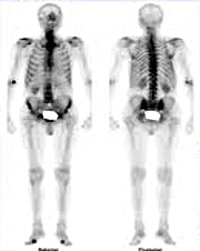

Статическая сцинтиграфия всего скелета позволяет одновременно определить воспаление суставов, вызванное ревматическим заболеванием. За 2-3 часа до начала исследования радиофармацевтический препарат вводится в вену пациента. Препарат распределяется по всему организму и накапливается в зонах концентрации наибольшего количества молодых костных клеток (где организм пытается восстановить участки, разрушенные воспалением). Специальной подготовки к опросу не требуется. Перед началом исследования вы должны опорожнить мочевой пузырь.

Статическая сцинтиграфия всего скелета представляет собой радионуклидную технику, основанную на введении и последующей оценке накопления в костных структурах остеотропной радиофармацевтической системы (RFP). Сцинтиграфия скелета выполняется с помощью гамма-камеры, с помощью которой можно фиксировать излучение изотопа и преобразовать его в графическое изображение. Сцинтиграфия скелета является наиболее востребованным и наиболее чувствительным методом ядерной медицины, который может обнаружить дисфункции.

В неизмененных костях скелета во время сцинтиграфии происходит симметричное накопление остеотропных радиофармацевтических препаратов. С помощью сцинтиграфии скелета исследуются суставы, длинные трубчатые кости, грудина, кости черепа, лопатки, кости таза, позвоночник. Сцинтиграфия скелета необходима для выявления новых областей роста (с распространением метастазов) и расщепления кости (при инфекциях, травмах, дегенеративных изменениях).

Обычно сцинтиграфия скелета определяется симметричным и равномерным распределением радиоактивного индикатора в костях. Области с наибольшим и наименьшим накоплением RFP на сцинтиграммах не обнаружены. Обнаружение повышенного накопления радиочастотных радиофармацевтических препаратов в некоторых областях костей («горячие» повреждения) может указывать на перелом, инфекцию, рак кости, артрит, болезнь Педжета. Недостаточное накопление радиоизотопа происходит при некоторых типах рака (множественная миелома) или при отсутствии кровоснабжения.